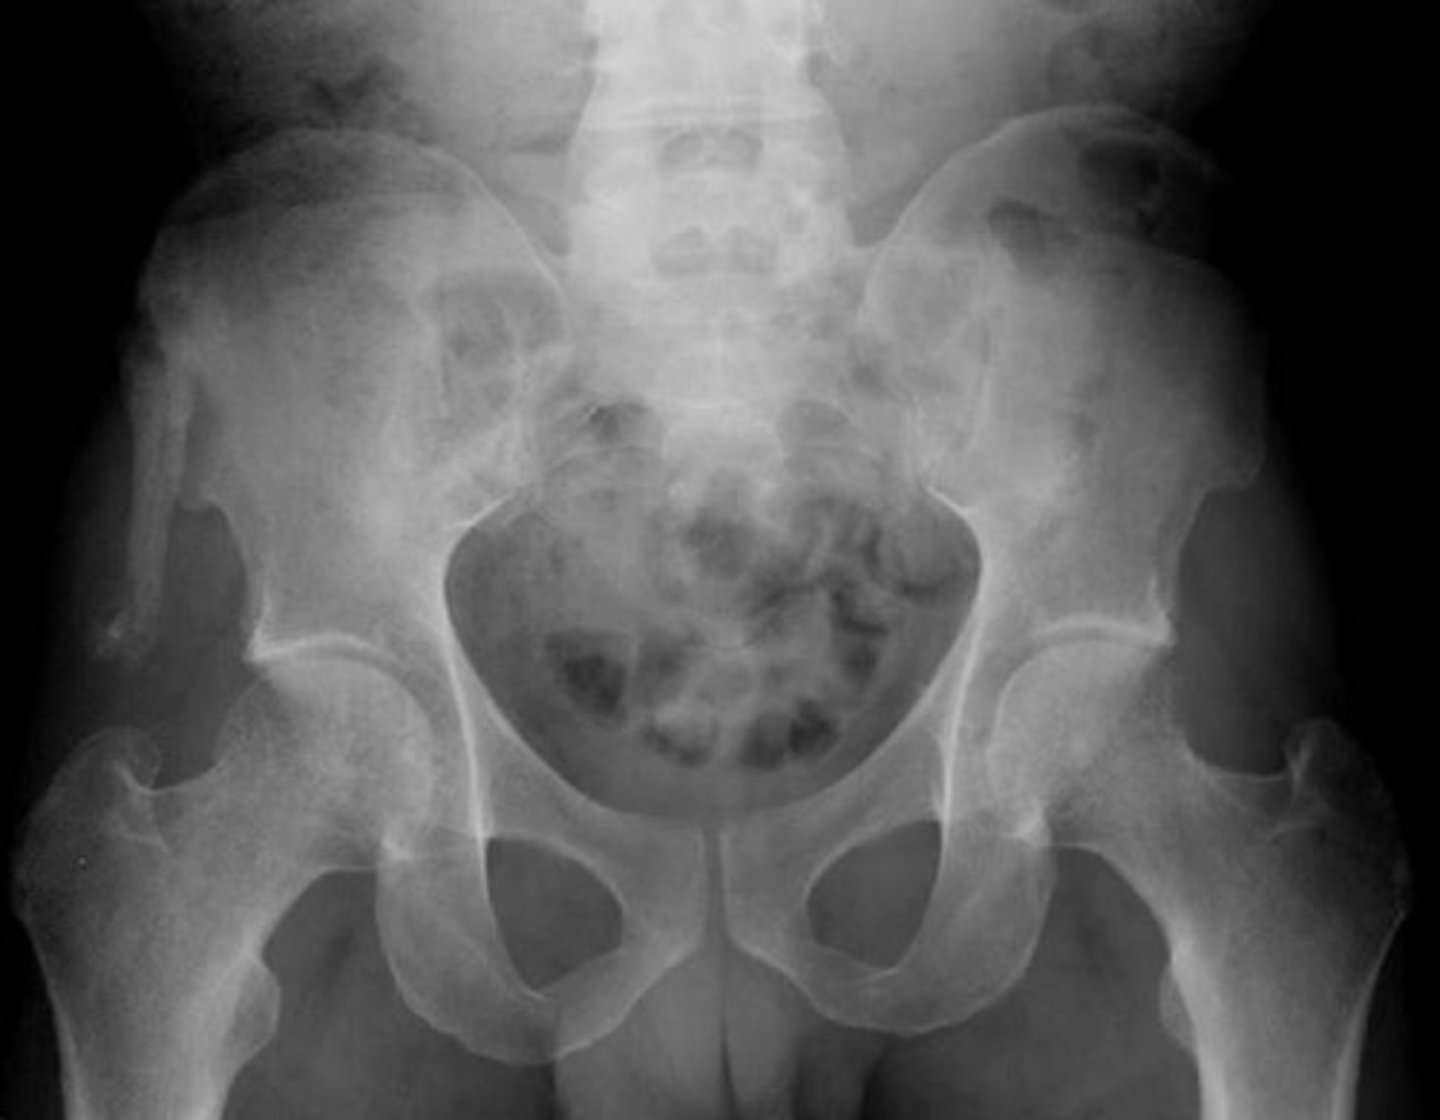

Female pelvis X-ray

(Female pelvis has a rounded (ovoid) shape)

What sex is this patient? How do you know?

Male pelvic x-ray

(Male pelvis has a triangular (android) shape)

Widened symphysis pubis and SI joint

What's going on here?